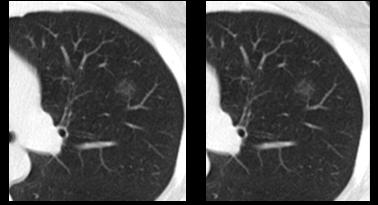

8mm磨玻璃结节,定期随访,CT发现结节实性成分增多,手术切除,病理为腺癌。

例如结节比较小,又在肺的中间位置靠近肺门,这种情况就算是恶性可能较大的8mm以上的磨玻璃结节,也不能发现后直接手术,需要观察后视病人的危险情况而定。唐小军教授解释道,若要切除长在中间位置的结节,则需肺叶或肺段切除,这种对患者的影响较大的手术,需评估危险因素后决定。

唐小军教授提到,对于肺结节手术,要根据肺结节的大小、位置、数量及分布来选择具体手术方式。

1.楔形切除:

结节位于肺周边部分;

结节直径<2cm的磨玻璃结节;